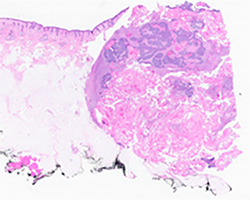

Subsequently she underwent left cheek wide local excision with left superficial parotidectomy, left neck dissection and left cervicofacial rotational flap. Gross examination revealed a discoid skin excision measuring 3.2 x 3.4 cm in surface with an excisional depth of 1.4 cm. Cut sections revealed a 1.6 x 1.6 x 0.7 cm centrally located tan, granular, semi-firm nodule abutting the deep margin (Fig. 4). Microscopic examination demonstrated a well circumscribed intradermal/ subcutaneous nodule with a thin fibrous capsule composed of peripherally located basaloid cells surrounding central collections of eosinophilic and shadow cells with numerous foreign body type giant cells consistent with pilomatricoma (Fig. 5A-5B)

Fig 4